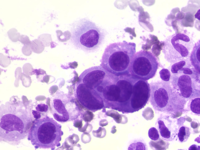

The image shows a small cohesive cluster of mesothelial cells with characteristic cell-to-cell windows. The cells are large with abundant basophilic cytoplasm and central round nuclei containing prominent nucleoli. Mild nuclear atypia is present, consistent with reactive changes. The background is hemorrhagic with numerous red blood cells. Overall, the features are in keeping with reactive mesothelial cells.